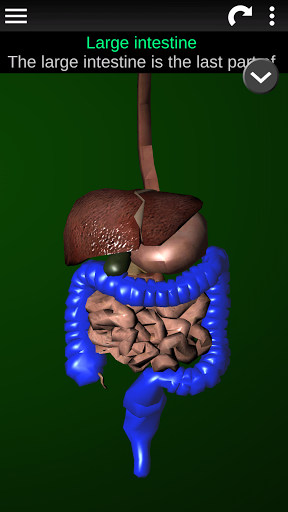

* Травна система, включаючи шлунок, тонку кишку, товсту кишку та анімацію цієї системи.

* Описи кожного органу.